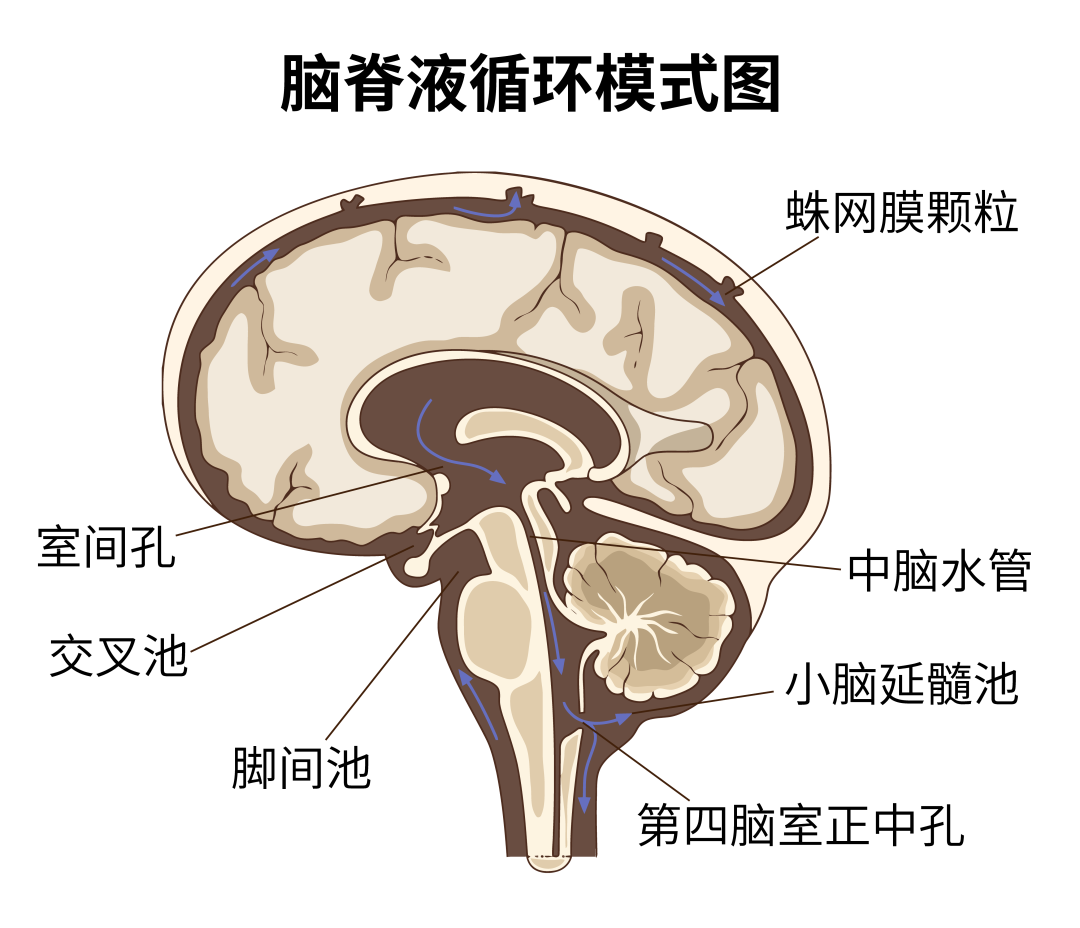

脑子里的“水”在医学上叫脑脊液,是无色的透明液体,人体每天都会产生一定量的脑脊液,其作用是为脑细胞提供营养,并运走脑组织的代谢产物,起到缓冲大脑和脊髓压力的作用。一般情况下,脑脊液是在颅内产生和循环,与外界不相通。

图源:深圳卫健委

人的大脑其实像个浮球一般漂浮在脑脊髓液之中,这能够最大限度地缓解外部冲击。

而脑脊液被硬膜囊包围,一旦硬膜囊破了,脑脊液逐渐漏出,脑组织就失去了浮力支撑,会跟神经形成拉力,使人出现头痛、恶心、耳鸣等症状。如不尽早处理,容易引起颅内出血、脑疝,甚至威胁生命。